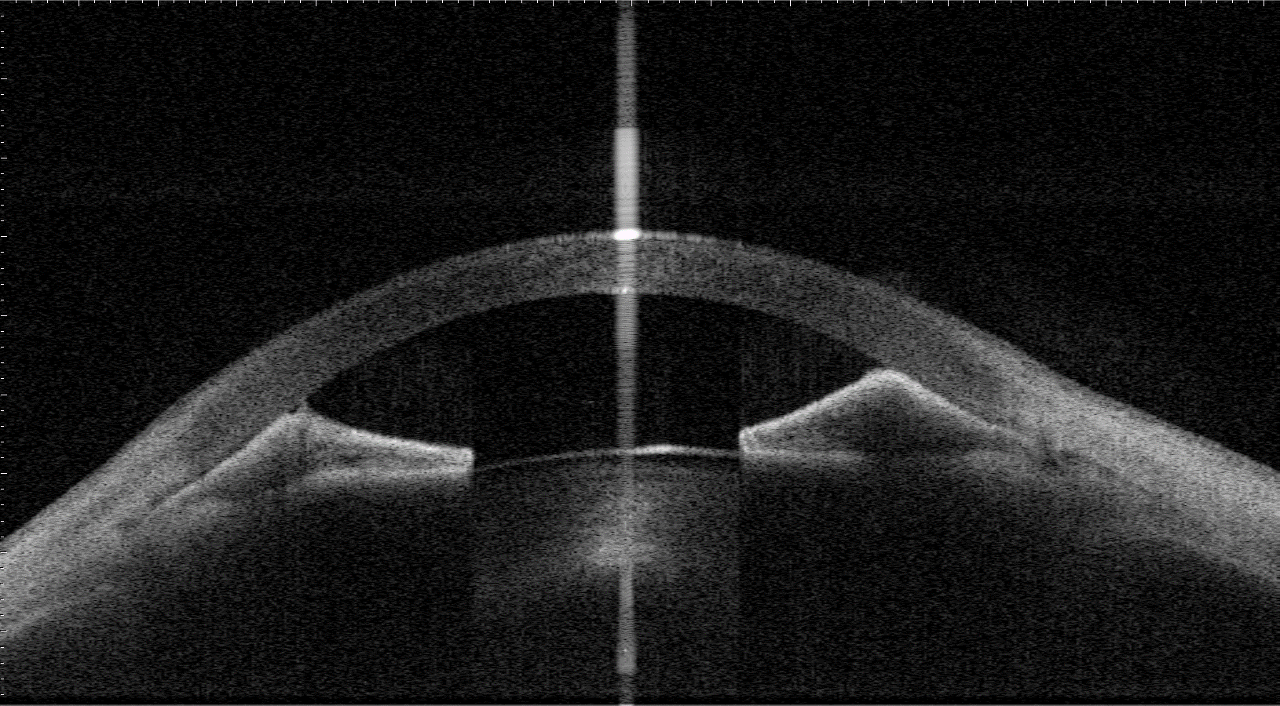

An eye with peripheral anterior synechia (PAS) captured by anterior-segment swept-source OCT. Image courtesy of Prof Clement Tham from Department of Ophthalmology and Visual Sciences, The Chinese University of Hong Kong.